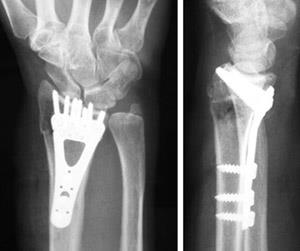

• Placa y tornillos: esta es la opción más frecuente para el tratamiento quirúrgico de fracturas de radio distal.

Una placa y tornillo mantienen las partes fracturadas en la posición correcta mientras se consolidan.